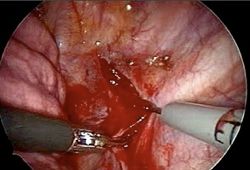

4. Endoscopic Thoracic Sympathectomy

ETS involves dissecting parts of the sympathetic nerve trunk to address severe hyperhidrosis (excessive sweating). A peculiar side effect of this surgery is the loss of the ability to blush, making it a cosmetic option for those who blush excessively. If performed on only one side, the patient would blush on the untreated side while the treated side remains unaffected. Consequently, the procedure is always conducted bilaterally.